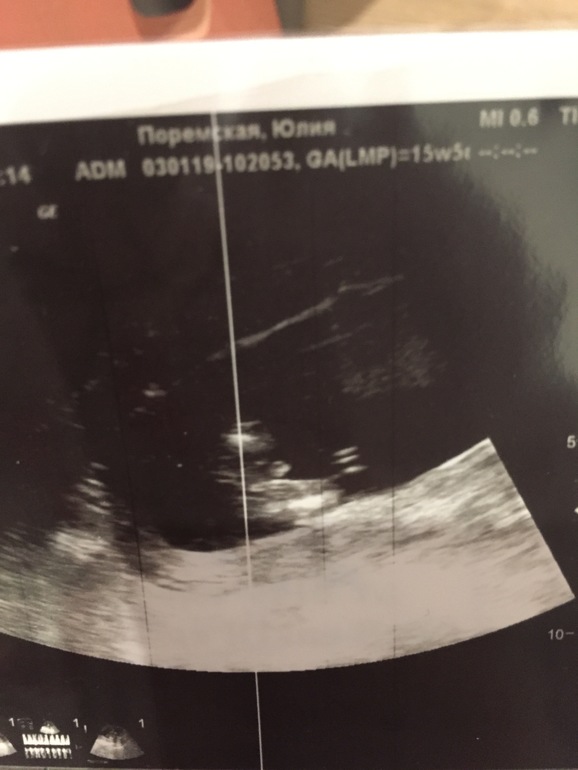

Итого наши итоги, в 12 недель КТР 54, чсс 150, твп 1,9 , носик 1,4. Жаль узист попался « не фотограф»)₽₽ фото выдал только головы ребенка. Ни мне не мужу экран не посчитал нужным показать. Но зато сказал что все хорошо) следующее в 16 недель.